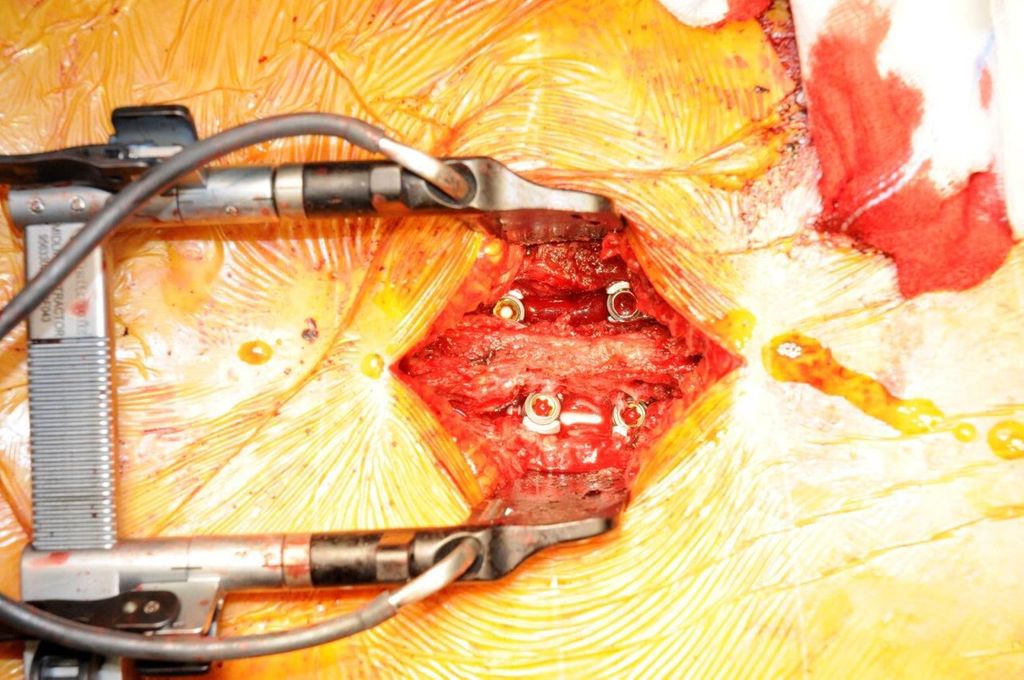

Beispiel für die Implantation zervikaler Pedikelschrauben. In diesem Fall kam es bei einem 61-jährigen Patienten 10 Jahre nach anteriorer zervikaler Diskektomie und Fusion (ACDF) C4/5 und ventraler Verplattung C4–6 zu einer Ankylosierung auch von C6/7. Nach Sturz kam es zu einer Fraktur bei C6/7 mit begleitender Bogenfraktur und auch Beteiligung der dorsalen Ligamenta (Abb. 1 und 2). Klinisch bestanden ausgeprägte Nackenschmerzen und kein neurologisches Defizit. Es wurde die Indikation der dorsalen Verschraubung von C4 auf Th1 gestellt. Intraoperativ wurde routinemäßig zusätzlich eine kleine Referenzschraube in einer Lamina – entfernt von der Dornfortsatz-Referenzklemme für die Navigation – gesetzt. Mit dieser konnte intraoperativ die Genauigkeit der Navigation exakt überprüft werden (Abb. 4 und 5). Mittels navigierter High-Speed-Fräse wurden die Schraubenkanäle vorgebohrt (Abb. 6), im Anschluss wurde der Bohrkanal ausgetastet und die Schrauben wurden implantiert. Abbildung 7 zeigt eine Röntgenkontrolle 3 Monate postoperativ.

Abb. 4: Screenshot der Navigationssoftware intraoperativ (Stealth Station S7). Es erfolgt die intraoperative Verifizierung der Navigationsgenauigkeit mittels kleiner Schraube in der Lamina, positioniert idealerweise entfernt von der Dornfortsatz-Referenzklemme. Die navigierte Fräse wird im Situs exakt auf die Schraubenmitte gerichtet, und die Navigation bestätigt die Genauigkeit | |